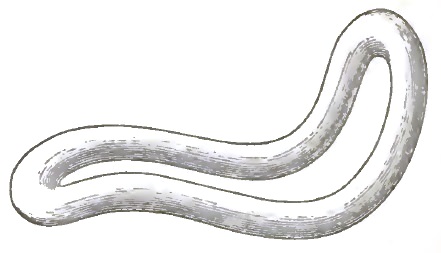

| 7. | THE EMMET CURVES (PESSARY) |

| 8. | THE ALBERT SMITH CURVES (PESSARY) |